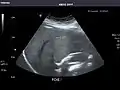

Aorta: Visualized portions normal in caliber, 16 x 15 mm.

Aorta